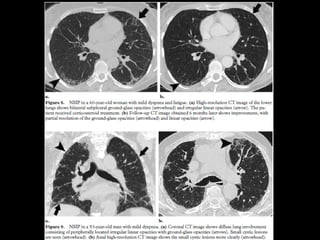

NSIP • + asociadoa otras condiciones esclerodermia, poliomiositis, dermatomiositis, toxicidad a drogas, inmunodeficiencia. • Mejor pronóstico • 40-50 h=m

NSIP TC • Vidrioesmerilado bilat y simétrico, LS Reticulación fina, BQ por tracción, disminuciónd e volumen pulmonar, panalización leve Consolidaciones Exacerbaciones menos comunes que FPI • Pronóstico depende del grado de fibrosis • Celular: 100% sv Fibrótico: 5 años SV

NSIP Histología • Continuode componente celular a fibrosis • Plasmocitos y linfocitos • Engrosamiento intersticial por acumulación de colágeno • Homogeneidad • Biopsia es incompatible con otros patrones